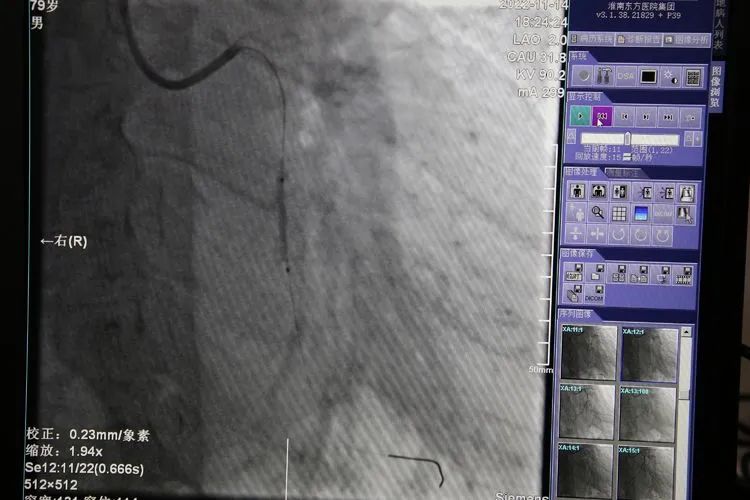

患者李师傅已经年近80高龄,此前因反复胸痛,在家人的陪同下,来到凤凰医院住院治疗。李师傅表示:每次发作时,都疼的大汗淋漓,故来到凤凰医院寻求治疗。完善冠脉造影可见:左冠状动脉回旋支近段90%挟窄,远段次全闭塞。回旋支远端病变血管细小,适合釆用了药物球囊扩张术;近端血管适合支架植入术。

集团心内科医疗中心汪蛟龙主任和凤凰医院高志纯主任高效协作,通过导管使药物球囊进入回旋支远段血管内,迅速到达病变部位,扩张成功。随后在回旋支近段植入一枚Firebira2 3.0×13m药物支架。手术持续约一个多小时,顺利将原本严重狭窄的冠脉血管狭窄解除,血运很快恢复正常。术后,岳某的胸痛症状得到了缓解。解决了心病困扰,老人也露出了久违的微笑。